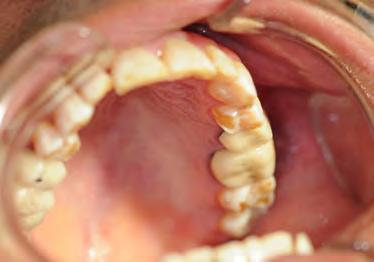

Two authors had access to the data and all information was de-identified. Study personnel made no contact with patients at any time throughout the study, and no PHI was recorded. Re corded data included diagnosis (clinical and/or pathologic), basic demographics (age, gender), and current prescription medica tions. For cases that were not biopsy-proven, the standard clinic protocol is that the clinical presentation must exhibit the charac teristic white Wickham striae for a patient to be given the clinical diagnosis of OLL or OLP (Figure 1). Any clinical diagnosis of OLL or OLP was rendered by one of four oral medicine experts in the Oral Medicine Clinic, and biopsy was performed in cases with any doubt.

Figure 1. Example of characteristic Wickham striae and reticular pattern on buccal mucosa used to clinically diagnose OLL and OLP cases. Erythematous areas also seen. Figure 2. Frequency and percent of study patients using specific medications with color-coded drug classes.